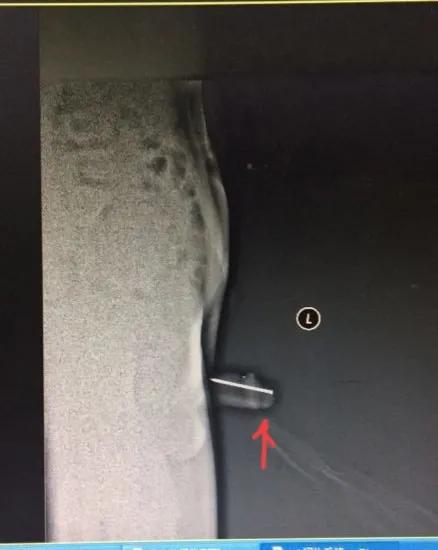

插入尿道的铁钉

上图取出的铁钉

钢针已进入盆腔